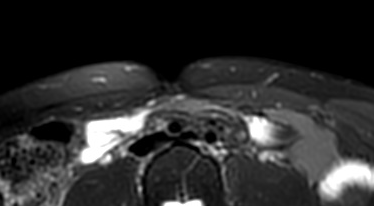

RM Avampiede

La struttura del piede, a causa dei suoi assi sempre variabili e discontinui) non consente la creazione di un protocollo standard per uno studio generale di tutto il piede. E’ quindi necessario dividere il piede in 4 zone principali: dita, metatarsi, tarso, caviglia; ciascuno con i suoi piani e protocolli specifici. STUDIO DEI METATARSI QUESTIONARIO…